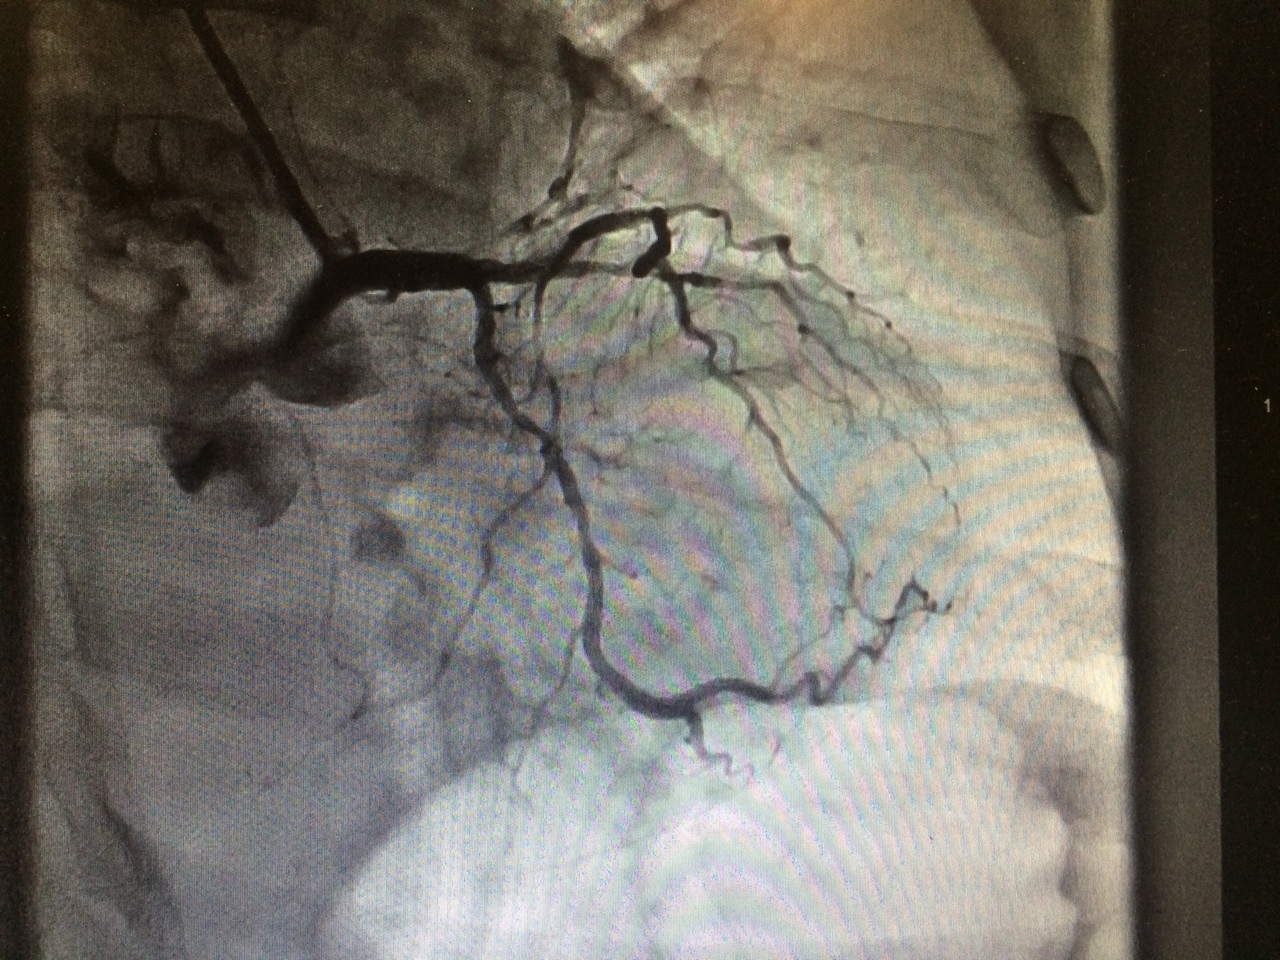

Vous transportez le patient en Fast Track vers la salle de coronarographie la plus proche.

Voici le résultat de l’examen

Occlusion aiguë thrombotique de la coronaire droite, flux TIMI 0 (thrombolysis in myocardial infarction zero)

Vous retenez donc le diagnostic d’infarctus inférieur Killip 1, de prise en charge tardive sur occlusion de la coronaire droite. Le patient est thrombo-aspiré et bénéficie de l’implantation d’un stent actif sur la coronaire droite moyenne. Le résultat angiographique est optimal avec rétablissement d’un flux TIMI 3. L’artère interventriculaire antérieur et circonflexe sont athéromateuses, sans lésion significative par ailleurs.